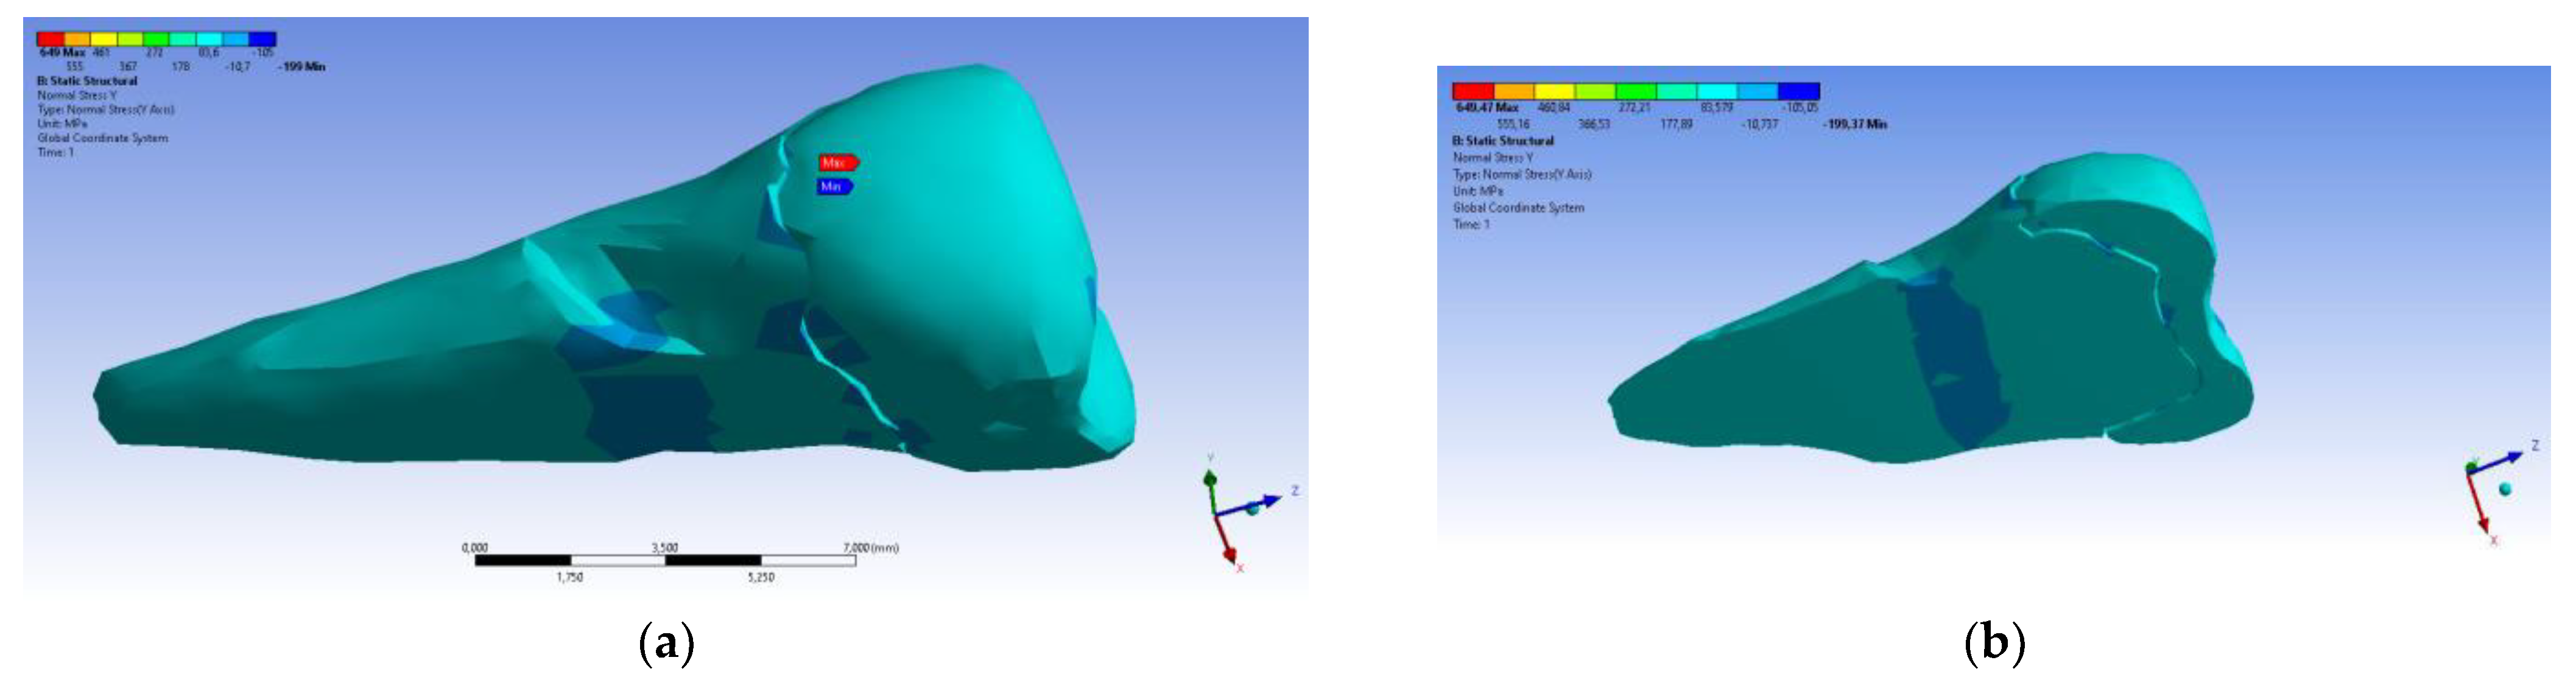

| Total Deformation | Deformation in X Direction | Deformation in Y Direction | Deformation in Z Direction | Equivalent Stress | Normal Stress X | Normal Stress Y | Normal Stress Z | Maximum Main Stress | Minimum Main Stress | Tangential Stress XY | Tangential Stress YZ | Tangential Stress XZ | |

|---|---|---|---|---|---|---|---|---|---|---|---|---|---|

| Minimum | 0 mm | −4.24 × 10−3 mm | −2.52 × 10−2 mm | −1.56 × 10−2 mm | 1.01 × 10−6 MPa | −35.6 MPa | −57.1 MPa | −104 MPa | −15.2 MPa | −152 MPa | −43.7 MPa | −39.6 MPa | −56.3 MPa |

| Maximum | 2.77 × 10−2 mm | 3.57 × 10−3 mm | 6.98 × 10−4 mm | 4.78 × 10−3 mm | 248 MPa | 61.5 MPa | 177 MPa | 72.2 MPa | 195 MPa | 21.4 MPa | 44.2 MPa | 117 MPa | 22.2 MPa |

| Minim. in | Cementum | Cementum | Enamel | Enamel | Cementum | Cementum | Enamel | Enamel | Enamel | Cementum | Enamel | Enamel | Cementum |

| Maxim. in | Enamel | Enamel | Cementum | Enamel | Cementum | Enamel | Enamel | Enamel | Enamel | Enamel | Cementum | Cementum | Cementum |

| Total Deformation | Deformation in X Direction | Deformation in Y Direction | Deformation in Z Direction | Equivalent Stress | Normal Stress X | Normal Stress Y | Normal Stress Z | Maximum Main Stress | Minimum Main Stress | Tangential Stress XY | Tangential Stress YZ | Tangential Stress XZ | |

|---|---|---|---|---|---|---|---|---|---|---|---|---|---|

| Minimum | 0 mm | −6.1 × 10−3 mm | −9.02 × 10−2 mm | −3.99 × 10−2 mm | 1.02 × 10−6 MPa | −112 MPa | −199 MPa | −278 MPa | −65.5 MPa | −470 MPa | −148 MPa | −176 MPa | −178 MPa |

| Maximum | 9.28 × 10−2 mm | 1.83 × 10−2 mm | 1.38 × 10−3 mm | 3.12 × 10−2 mm | 780 MPa | 61.5 MPa | 649 MPa | 304 MPa | 704 MPa | 73.8 MPa | 134 MPa | 370 MPa | 78.6 MPa |

| Minim. in | Cementum | Cementum | Enamel | Enamel | Cementum | Cementum | Enamel | Enamel | Enamel | Cementum | Enamel | Enamel | Cementum |

| Maxim. in | Enamel | Enamel | Cementum | Enamel | Cementum | Enamel | Enamel | Enamel | Enamel | Enamel | Cementum | Cementum | Cementum |